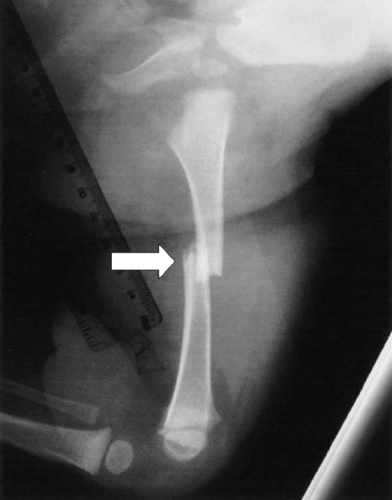

Pathological Fracture - आजारामुळे हाडे कमजोर होऊन तुटणे.

Spiral Fracture - हाडाच्या एखाद्या भागाला पीळ पडणे.